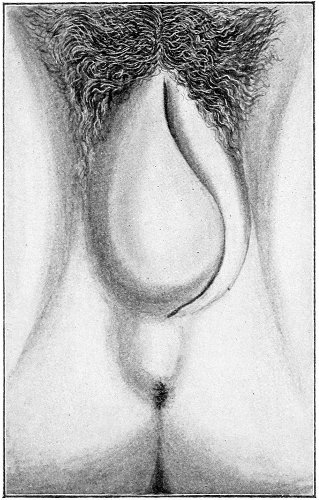

Suppuration of the vulvo-vaginal gland is accompanied by marked swelling and peripheral edema. The swelling may extend to the anus, and is of characteristic shape (Fig. 17). The pain is always severe. Fluctuation is first apparent on the inner surface of the labium majus. If the condition is not treated, one or more fistulous openings appear below the orifice of the duct, and the pus is discharged. The condition then becomes chronic. The fistulous openings persist. Acute inflammation disappears from the gland, leaving it in a condition of hypertrophic induration. A thin, milky or greenish, purulent fluid may be pressed out of the duct or the fistulous openings. Infection from this discharge may be communicated to man, or may ascend the genital 40 tract, producing inflammation of the endometrium or of the Fallopian tubes.

Fig. 17.—Abscess of right vulvo-vaginal gland.

In abscess of the vulvo-vaginal gland a free incision should immediately be made into the labium at the junction of the skin and the mucous membrane. The interior should be wiped out with pure carbolic acid and the cavity packed with gauze. If the disease is first seen in the chronic stage, after the abscess has evacuated itself, the only method of cure is to excise, with curved scissors, the whole of the indurated gland, the duct, and the fistulous tracts. The wound may be left open and packed, or it may be closed immediately with buried catgut sutures.

Cysts of the Vulvo-vaginal Glands.—Cysts may 41 occur in the duct of the vulvo-vaginal gland or in the gland itself. Cysts of the duct are small—about the size of a chestnut. They are situated superficially, lying immediately under the mucous membrane of the vagina at the base of the labium minus.

Fig. 18.—Cyst of the right vulvo-vaginal gland (Hirst).

Cysts of the gland may be unilocular if formed at the expense of a single lobule of the gland, or multilocular if several lobules enter into their formation. These cysts may attain the size of the fetal head (Fig. 18).